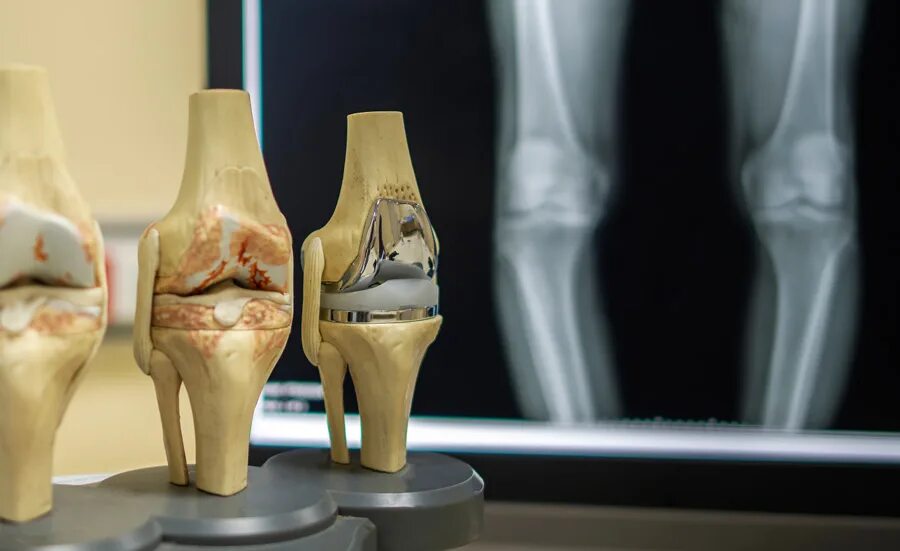

Хобл 1 группа инвалидности. инвалидность 2 группы хобл. хобл группа инвалидности. 2 группа инвалидности при хобл.Инвалидность при артрозе 3 степениГонартроз наколенник коленного. гонартроз 3 степени ортез. бандаж на коленный сустав при артрозе 2 степени.2 группа инвалидности. 3 группа инвалидности. инвалидность группы и степени. 2 группа 3 степень инвалидности.Группы инвалидности по степени трудоспособности. степени инвалидности 3 группы. 2 группа 3 степень инвалидности. инвалидность 1 и 2 степени.Инвалидность при артрозе 3 степениИнвалидность при гонартрозе. нетрудоспособность при остеоартрозе. инвалидизация при артрозе. остеоартроз инвалидность.Коксартроз тазобедренного сустава 2 степени инвалидность. инвалидность 3 степени при коксартрозе тазобедренного. инвалидность при коксартрозе тазобедренного сустава.Инвалидность при артрозе 3 степениГонартроз инвалидность. инвалидизация при артрозе. остеоартроз инвалидность.Коксартроз тазобедренного диагноз. коксартроз тазобедренного сустава инвалидность. коксартроз 2 степени тазобедренного сустава дают ли инвалидность. коксартроз 3 степени тазобедренного сустава инвалидность.Инвалидность при артрозе 3 степениИнвалидность остеоартрит. инвалидизация при артрозе.Инвалидность заболевания. группы инвалидности заболевания. инвалидность по общим болезням. инвалидность заболевания по группам.Инвалидность при артрозе 3 степениГонартроз коленного сустава 2. гонартроз коленного сустава 3. гонартроз 3 степени рентген.1 группа б инвалидности. сетка инвалидности. меланома первая группа инвалидности. инвалидность при трахеостоме.2 группа 3 степень инвалидности. инвалидности 1 2 3 группы пример. категории болезней для инвалидности 1 группы. инвалид 2 группы 3 степени.Инвалидность при гонартрозе. инвалидность при гонартрозе 3 степени.Гипертоническая болезнь 3 риск 4 инвалидность. 3 стадия гипертонии группа инвалидности. гипертоническая болезнь 3 стадии 1 степени риск 4 группа инвалидности. гипертоническая болезнь 2 стадия 2 степени группа риска 3.Группы инвалидности. получение инвалидности. инвалидность группы инвалидности. 2 группа инвалидности это какие заболевания.Коксартроз тазобедренного сустава 3. коксартроз эндопротезирование тазобедренного сустава. диспластический коксартроз тазобедренного сустава. коксартроз тазобедренного сустава 2 степени инвалидность.Инвалидность при артрозе 3 степениМедико-социальную экспертизу для получения инвалидности. мсэ 1 группа инвалидности. медико-социальная экспертиза (мсэ): инвалид, инвалидность. справка об инвалидности ребенка инвалид детства.Коксартроз 2 степени тазобедренного. остеонекроз тазобедренного сустава 2 -3 степени. асептический некроз бедренных костей. коксартроз асептический некроз головки.Инвалидность 2 группы онкология. вторая группа инвалидности по онкологии. 1 группа инвалидности по онкологии. инвалидностью ii группы.2 группа 3 степень инвалидности. инвалидность 2\2 гр. группа инвалидности льготы. 1 группа инвалидности.Инвалидность при артрозе 3 степениАртроз тазобедренного сустава 3 степени положена ли инвалидность. коксартроз 3 степени тазобедренного сустава сняли инвалидность. коксартроз эндопротезирование. коксартроз после эндопротезирования диагноз.Инвалидность при артрозе 3 степениИнвалидность при артрозе 3 степениКоксартроз тазобедренного сустава инвалидность. коксартроз тазобедренного 4 степени инвалидность. инвалидность 3 степени при коксартрозе тазобедренного. коксартроз тазобедренного сустава 2 степени инвалидность.Инвалидность при артрозе 3 степениИнвалидность при артрозе 3 степениМедико-социальная экспертиза (мсэ): инвалид, инвалидность. втэк 3 группа инвалидности. 2 группа инвалидности. мсэ 2 группа инвалидности.Диспластический коксартроз рентген. снимки коксартроза 1.2.3 степени тазобедренного сустава. коксартроз 4 степени тазобедренного. диспластический коксартроз тазобедренного сустава рентген.Инвалидность при артрозе 3 степениИнвалидность при артрозе 3 степениФункциональные классы нарушения функции суставов. степени функциональной недостаточности суставов. степени нарушения функции суставов. функциональное нарушение суставов классификация.Группы инвалидности. вторая группа инвалидности. легкая группа инвалидности. дают ли инвалидность.Получение группы инвалидности. инвалидность по группам. заболевания по инвалидности. сроки получения инвалидности.Инвалидность при артрозе 3 степениИнвалидность при артрозе 3 степениИнвалидность при артрозе 3 степениИнвалидность при артрозе 3 степениСтенокардия формулировка диагноза. инвалидность при ибс. инвалидность заболевания по группам. группа инвалидности при стенокардии.Справка об инвалидности. мсэ и инвалидность по зрению. 2 группа инвалидности. 3 группа инвалидности.Инвалидность при артрозе 3 степениИнвалидность 2 группы онкология. группа инвалидности при болезни. 1 группа инвалидности. группы инвалидности при онкологии группы.Инвалидность при артрозе 3 степениВторая группа инвалидности бессрочно. справка об инвалидности бессрочно. 3 группа инвалидности бессрочно. бессрочная инвалидность 2 группы.Продольное плоскостопие 1. продольно-поперечное плоскостопие 2 степени. продольным или поперечным плоскостопием ii степени. продольное плоскостопие деформация стопы.1 2 3 группа инвалидности. инвалидность группы и степени. степень инвалидности по группам. критерии присвоения группы инвалидности.Первичный гонартроз двусторонний. гонартроз коленного сустава. деформирующий артроз 2. деформирующий артроз 1-2 степени.Инвалидность при артрозе 3 степениПеречень заболеваний для инвалидности. инвалидность 2 группы перечень заболеваний. вторая группа инвалидности болезни. инвалидность 1 и 2 группы перечень заболеваний.Втэк 3 группа инвалидности. форма справки мсэ по инвалидности. мсэк бессрочная инвалидность 2 группы. справка мсэ об инвалидности 1 группы.Справка об инвалидности 3 группы. инвалидность группы инвалидности. вторая группа инвалидности. группа инвалидности бессрочно.Инвалидность при артрозе 3 степениИнвалидность при артрозе 3 степениСтепень инвалидности при остеохондрозе. инвалидность при 3 степени остеохондроза. полагается ли группа инвалидности при заболеваниях позвоночника?. инвалидность по сколиозу 3.Группы инвалидности. третья группа инвалидности. инвалидность по группам. вторая группа инвалидности.Дают ли при инфаркте 3 группу инвалидности. инфаркт миокарда инвалидность. положена ли инвалидность после инфаркта миокарда и стентирования. инвалидность по инфаркту миокарда.Группы инвалидности. степени инвалидности. инвалидность группы и степени. 1 группа инвалидности.Инвалидность при артрозе 3 степениИнвалидность при артрозе 3 степениИнвалидность при артрозе 3 степениИнвалидность при переломе бедра. отсутствие конечности группа инвалидности. группа инвалидности при ампутации голени. группы инвалидности ампутация.Инвалидность группы инвалидности. группа инвалидности при болезни. диагнозы инвалидов. f70 диагноз инвалидность.Инвалидность при артрозе 3 степени